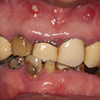

4.支座的连结

作为人工牙齿的支座的植入部分(abutment)与固定物连接。